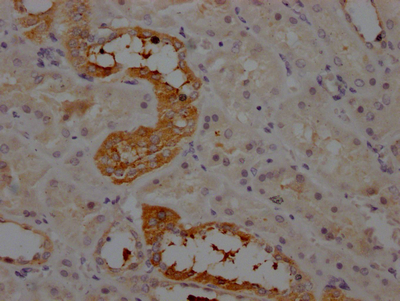

CSB-RA263831A0HU

IHC image of CSB-RA263831A0HU diluted at 1:100 and staining in paraffin-embedded human kidney tissue performed on a Leica BondTM system. After dewaxing and hydration, antigen retrieval was mediated by high pressure in a citrate buffer (pH 6.0). Section was blocked with 10% normal goat serum 30min at RT. Then primary antibody (1% BSA) was incubated at 4℃ overnight. The primary is detected by a Goat anti-rabbit IgG polymer labeled by HRP and visualized using 0.05% DAB.